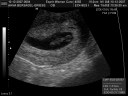

Don’t worry, this won’t be a ‘year in review’ post, but we will revisit last Sept quickly. For several reasons we were extremely excited and very nervous about the news last September. We decided to tell just our parents and immediate family that we were expecting…Ahna reminded me yesterday that we told our parents on my birthday. We waited to tell our friends until after the first trimester was complete just to make sure that everything was on the up and up. Boy was it ever. We remember one ultrasound where Ezra was jumping up and down and doing head-over-heel flips…full of anticipation, we wondered what it would be like to see it in person.

Here’s the first and the latest pictures of Ezra: